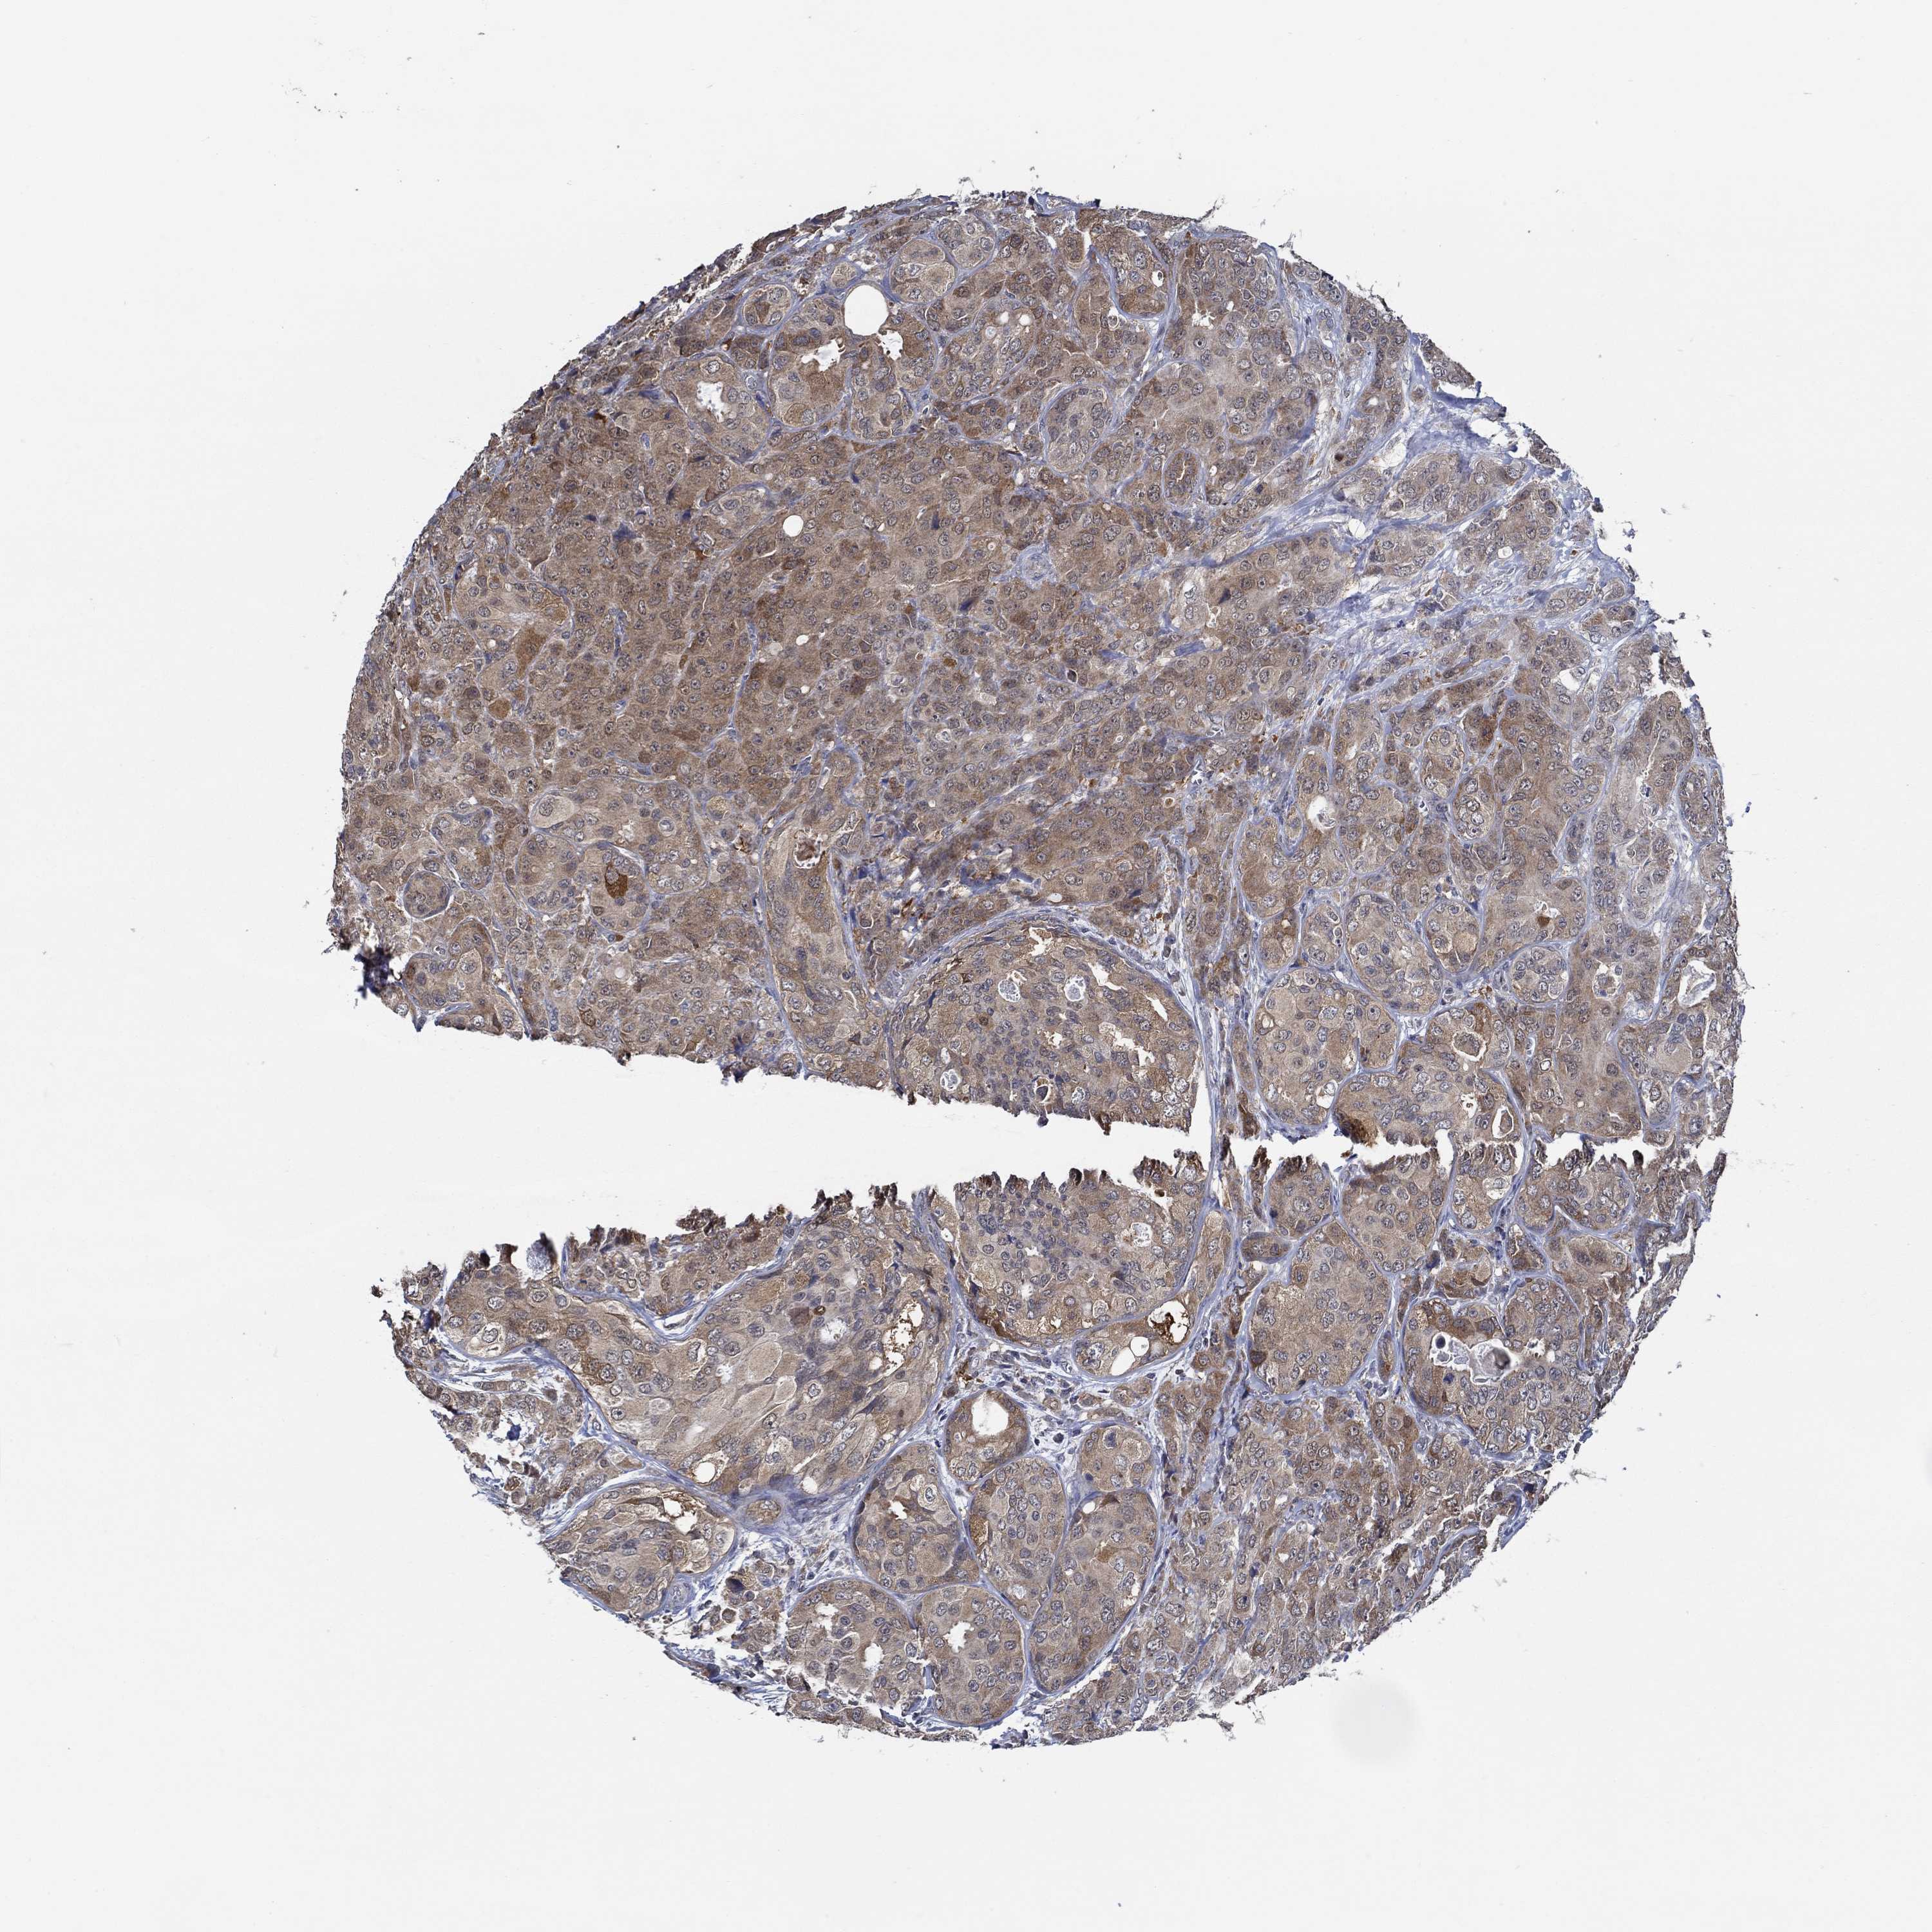

CANCER BREAST CANCER Show tissue menu

BRCA TCGA BRCA VALIDATION PROTEIN EXPRESSION

Breast cancer

Human cancer

DACT1 is not prognostic in Breast Invasive Carcinoma (TCGA)